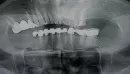

Прикрепленые фото

По данному рентгеновскому снимку практически все корневые каналы зубов, пролечены некачественно, и определить какой именно зуб вызывает подобные жалобы дистанционно невозможно. Необходим осмотр и компьютерная томография. Проконсультируйтесь очно с опытным врачом-стоматологом.